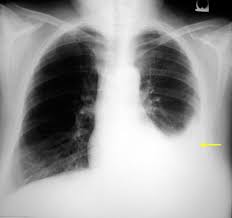

A pneumothorax means a collapsed lung. न्यूमोथोरैक्स का अर्थ है “ढह गया फेफड़ा”। A pneumothorax occurs when air leaks into the space between your lung and chest wall. न्यूमोथोरैक्स तब होता है जब हवा आपके फेफड़े और छाती की दीवार के बीच की जगह में लीक हो जाती है। This air pushes on the outside of your lung and makes it collapse. यह हवा आपके फेफड़े को बाहर से धकेलती है और इसे ढहा देती है। A pneumothorax can be a complete lung collapse or a collapse of only a portion of the lung. एक न्यूमोथोरैक्स फेफड़े का पूर्ण पतन या फेफड़े के केवल एक हिस्से का पतन हो सकता है।